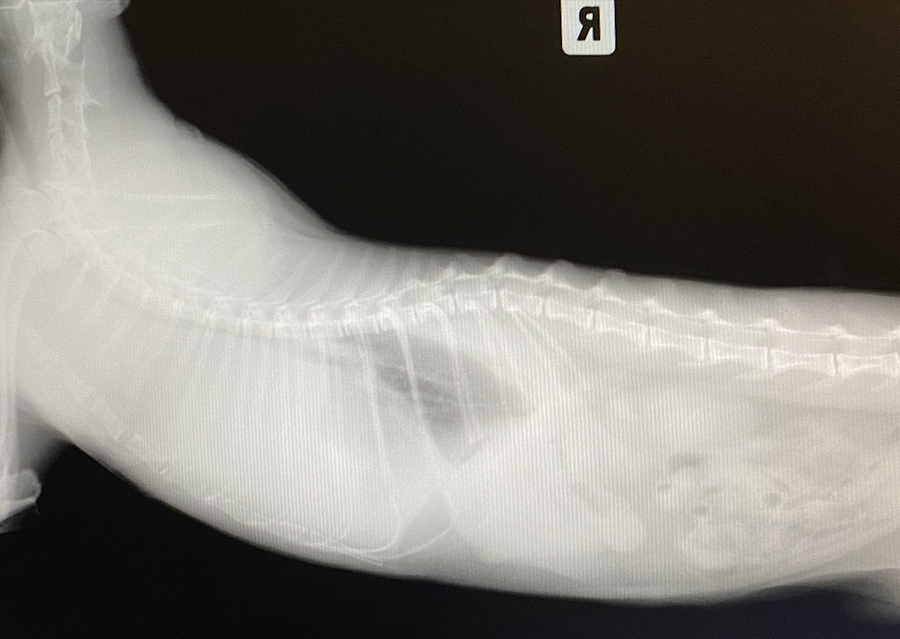

В первую очередь животному был выполнен рентген грудной полости в прямой и боковой проекциях, который выявил плевральный выпот. Было принято решение о срочном проведение торакоцентеза. Было удалено 100 мл кровянистой жидкости с левой стороны и 80 мл с правой стороны. Данная жидкость была отправлена на цитологию, а также на ПЦР для выявления короновирусной инфекции кошек. Был установлен внутривенный катетер и взяты анализы крови на биохимический и клинический анализы, а также на лейкемию (ИФА), иммунодефицит (ИХА), титр антител к коронавирусу (ИФА). Давление животного в результате измерения было в норме. Животное было оставлено в стационаре для проведение внутривенной инфузии, оксигенации и контроля состояния. В стационаре состояние животного оставалось стабильным, одышка уменьшилась (до 33 ДД). В течение суток состояние животного нормализовалось под действием мочегонных, обезболивающий, успокоительных препаратов, а также внутривенных инфузий с питательными веществами и антиоксидантами.

На следующий день часть анализов были готовы, по биохимическому и клиническому анализу значимых отклонений не было (кроме гемоглобина и гематокрита, которые были на нижней границе нормы). Цитологическая картина плеврального выпота была характерная для лимфомы крупноклеточной. Повторные рентгены грудной полости выявили образование в грудной полости. Через сутки был готов результат анализа на лейкемию, который показал положительный результат. Коронавирусная инфекция и вирусный иммунодефицит были отрицательными.